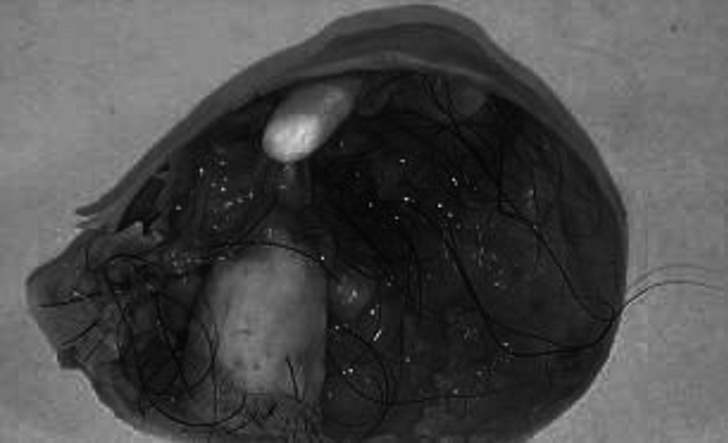

Pero hoy finalmente descubrió qué padecía. De acuerdo a la revista especializada Woman’s Health, los médicos al fin hallaron el motivo de sus insoportables dolores: un gran quiste dermoide en el ovario derecho.

De acuerdo al sitio, esta malformación contenía restos de dientes y pelos alojados en su organismo. La misma joven describió este quiste como “un pequeño monstruo“.

La doctora Megan Sheldon explicó que este si bien este quiste es benigno (sin células cancerígenas), debido a sus dimensiones, podía llegar a ser peligroso.

La especialista recomendó extirparlo lo antes posible, ya que podría continuar provocando problemas en sus ovarios e incluso desarrollar un cáncer.